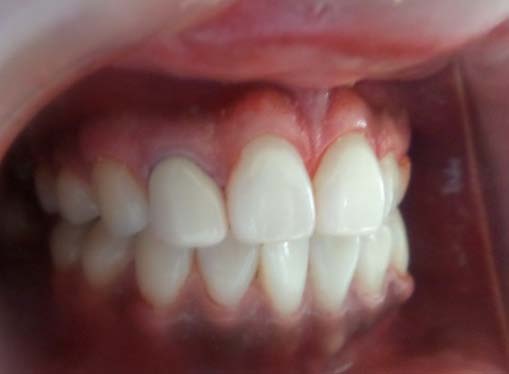

After post obtuaration restoration, crown preparation was done and PFM crown placed. During the first visit after isolation was done using rubber dam (Hygiene Dental Dam, Coltene Whaledent, Germany). A cavity was prepared and working length was determined using apex locator (Root ZX II, Morita Tokyo, Japan) (figure 6). Biomechanical preparation was done using hand stainless steel file till 70K wrt 21 and till 50K wrt 22 along with the copious irrigation with 5.25% sodium hypochlorite. An intracanal medicament dressing of calcium hydroxide was given and the tooth was sealed with provisional material.

After 7 days the intracanal dressing was changed for another obtaining by mixing calcium hydroxide powder and tooth was sealed. On third visit the intracanal dressing was removed and the canal was irrigated with 17% EDTA and master cone radiograph was taken (figure 7). 21 was obturated with the lateral cold compaction technique and the portion of the canal below the resorptive defect was obturated with gutta percha (Dentsply, Maillefier Germany) and A H plus sealer (Dentsply, Maillefier Germany) using sectional condensation technique and the remaining canal was obturated with thermoplastized gutta percha technique. Then final restoration with composite was done followed with prosthesis (figure 8). In 21 root canal treatment was started with straight line access, working length was determined using radiograph(figure 10) and bleeding point was check using paper point. Biomechanical was done till 80K stainless steel file under copious irrigation with saline. Calcium hydroxide intracanal medicament was place for 2 week and cavity was sealed with temporary material. Following copious irrigation with 5% sodium hypochlorite, calcium hydroxide powder mix was renewed after a week.

Calcium hydroxide was renewed two times in 2 mon due to the exudation into the canal. At the 3 mon visit, white MTA (ProRoot MTA, Dentsply, TN, US) was prepared according to the manufacturer's recommendations and filled incrementally to the canal orifice with vertical condensation using the pluggers. Intraoperative radiographies revealed that MTA filled the canal and the resorption defect. A wet cotton pellet was put on the MTA, and the cavity was sealed with the temporary restorative material. After 7 days, the cavity was restored using a composite resin (figure11) filling (Supreme, 3M ESPE, Dental Products, MN, USA) and PFM crown was placed.